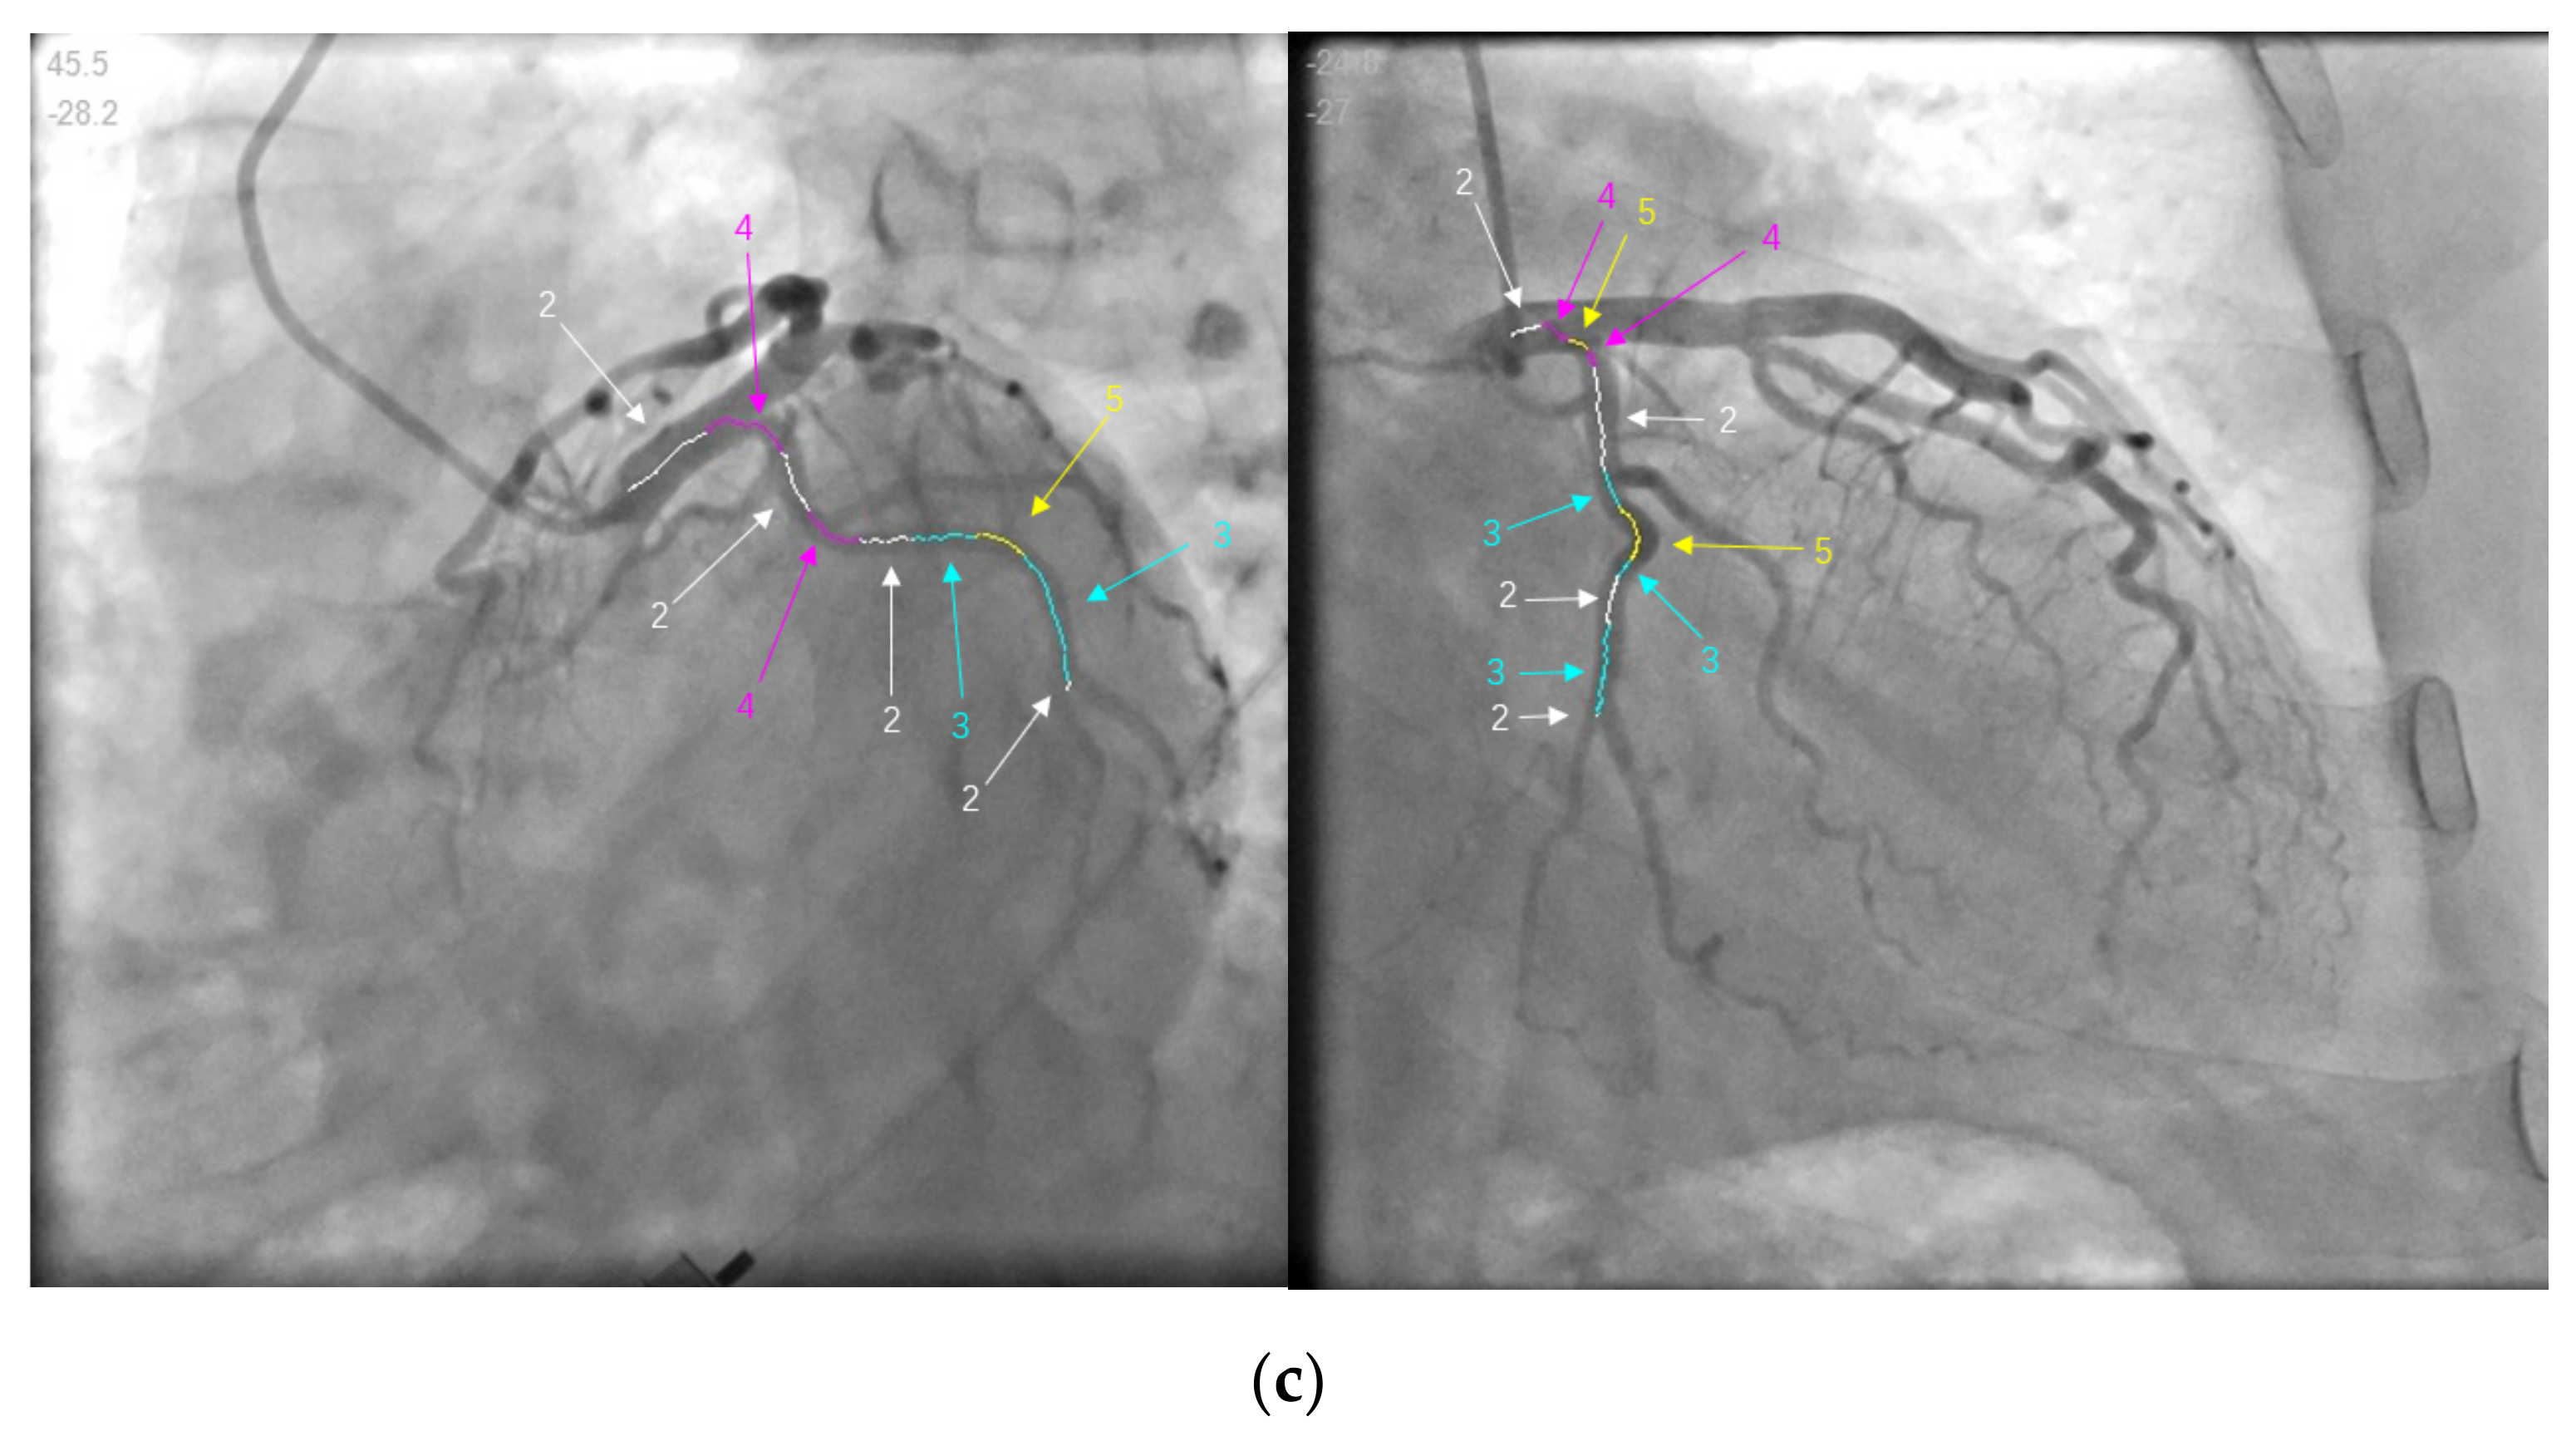

| Data.1 | (a) | 45.5 | −28.2 | 1200 | 749 |

| (b) | −24.8 | −27 | 1147 | 844 | |

| Data.1 | (a) | Match 1 | 1.90582 | 0.00175 | 0.79173 | 0.49422 | 83.1266 |

| Match 2 | 0.70741 | 0.00123 | 0.13104 | 0.1651 | 4.2336 | ||

| Match 3 | 0.6653 | 0.06917 | 0.12584 | 1.99264 | |||

| (b) | Match 1 | 1.74575 | 0.0016 | 0.73019 | 0.4522 | / | |

| Match 2 | 0.66112 | 0.00116 | 0.12136 | 0.1535 | / | ||

| Match 3 | 0.62295 | 0.06439 | 0.11788 | / | |||

| Data.2 | (c) | Match 1 | 5.66455 | 0.0334 | 2.72141 | 1.83636 | 824.806 |

| Match 2 | 1.06809 | 0.00136 | 0.22034 | 0.29041 | 10.4045 | ||

| Match 3 | 0.80592 | 0.09791 | 0.19193 | 3.64186 | |||

| (d) | Match 1 | 5.76568 | 0.0333 | 2.76739 | 1.87068 | / | |

| Match 2 | 1.07169 | 0.00135 | 0.22205 | 0.29158 | / | ||

| Match 3 | 0.81107 | 0.09869 | 0.19298 | / | |||

| Data.3 | (e) | Match 1 | 3.31963 | 0.00151 | 1.35754 | 1.09306 | 350.884 |

| Match 2 | 0.09431 | 0.02394 | 0.01995 | 0.11051 | |||

| Match 3 | 0.079089 | 0.02334 | 0.0186 | 0.10128 | |||

| (f) | Match 1 | 3.51223 | 0.00161 | 1.43727 | 1.15846 | / | |

| Match 2 | 0.09964 | 0.02519 | 0.02092 | / | |||

| Match 3 | 0.08201 | 0.02456 | 0.01947 | / |